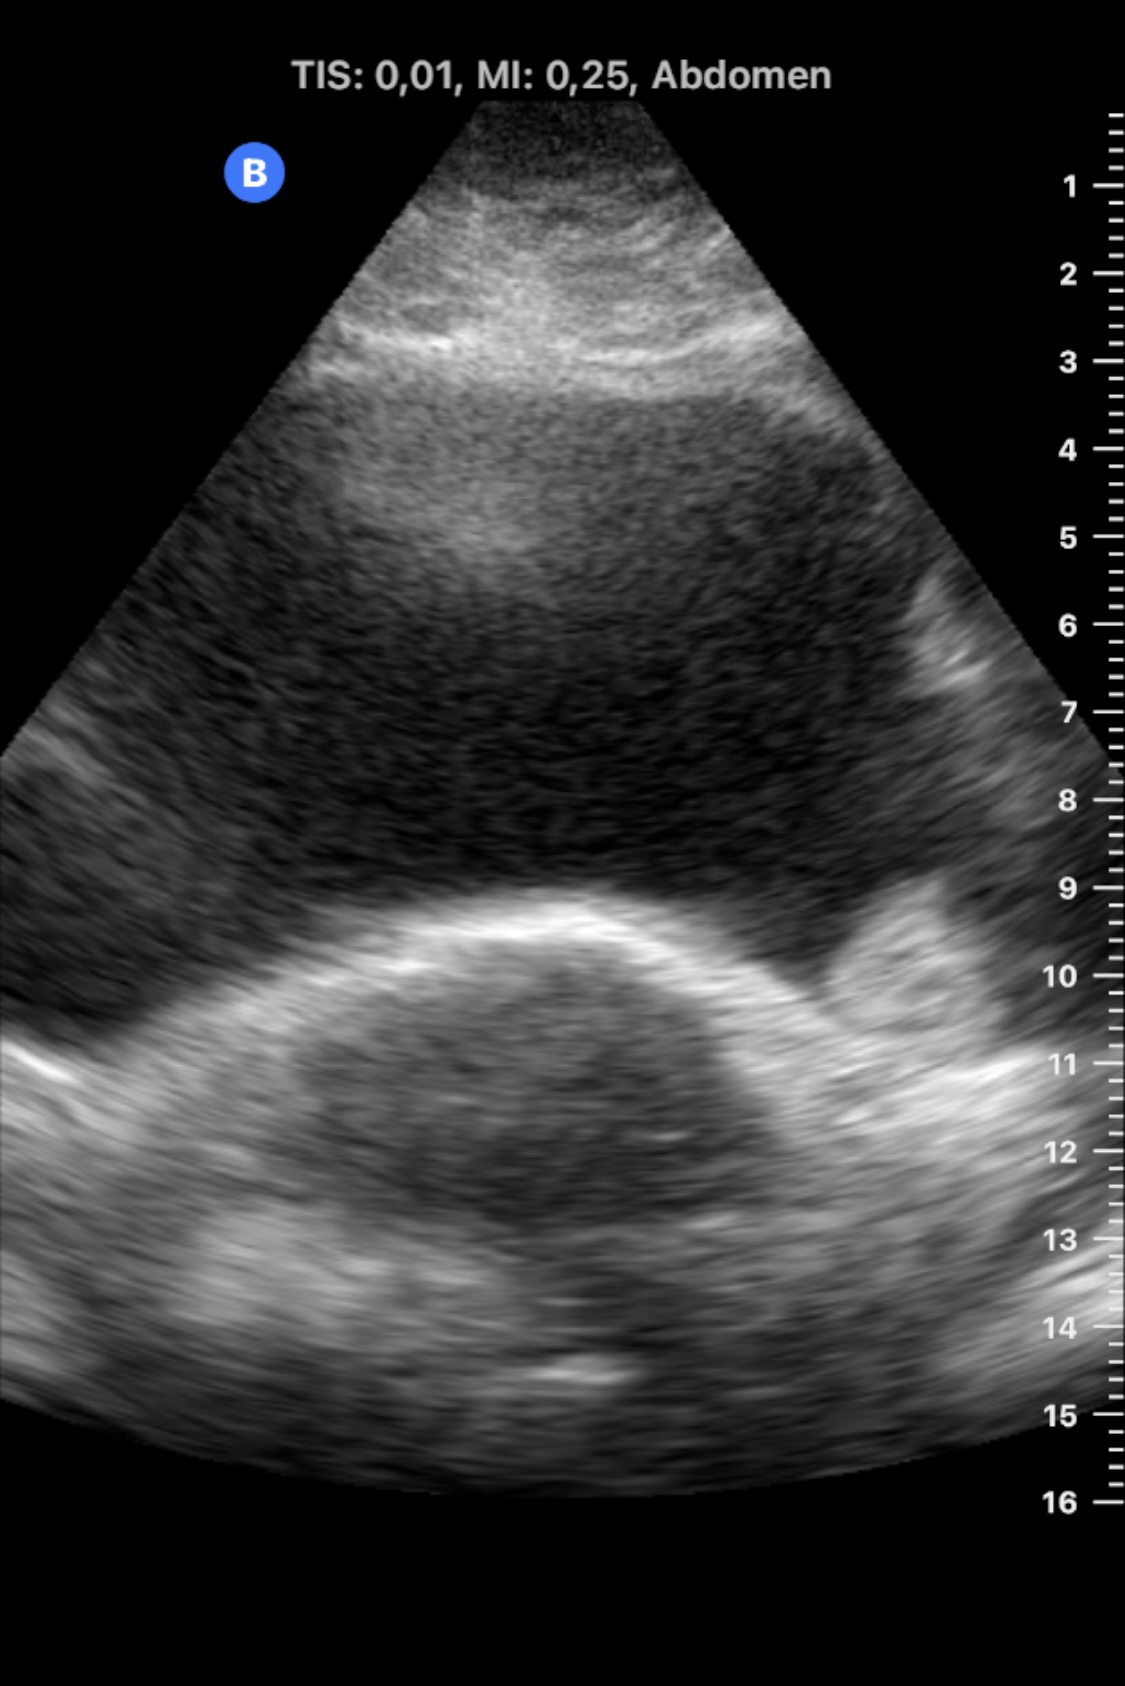

Realizamos Ecografía clínica en consultorio rural, con sonda portátil: riñones con ecoestructura, tamaño y localización normales. Ausencia de dilatación de vías urinarias. Vejiga bien repleccionada en la que se objserva en la base izquierda de la vejiga una imagen homogénea, sólida, intravesica y dependiente de la mucosa, sin sombra acústica posterior. No se modifica con el cambio postural de la paciente.

En urgencias se realizó ecografía reglada: «...Vejiga poco replecionada, poco valorable en este estado, observándose en su margen inferior izquierdo, lo que parece corresponder con una lesión de partes blandas de unos 27,5 x 14 x 26,2 mm y márgenes lobulados, que no se modifica con los cambios posturales».